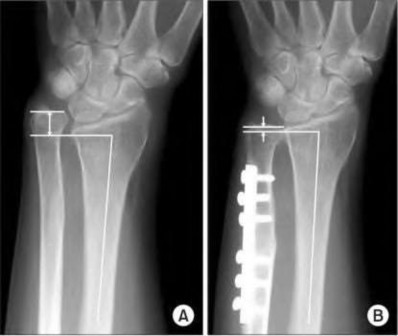

A 22-year-old male falls onto an outstretched hand and sustains a displaced fracture through the proximal pole of the scaphoid. Avascular necrosis of the proximal pole is highly likely due to the disruption of its primary vascular supply. Which vessel provides this critical retrograde perfusion?

Explanation

The primary blood supply to the scaphoid is from the dorsal carpal branch of the radial artery, which enters the dorsal ridge of the scaphoid at the waist and courses proximally. This retrograde blood flow makes proximal pole fractures highly susceptible to avascular necrosis and nonunion. The superficial palmar branch provides a minor supply (about 20%) to the distal pole.